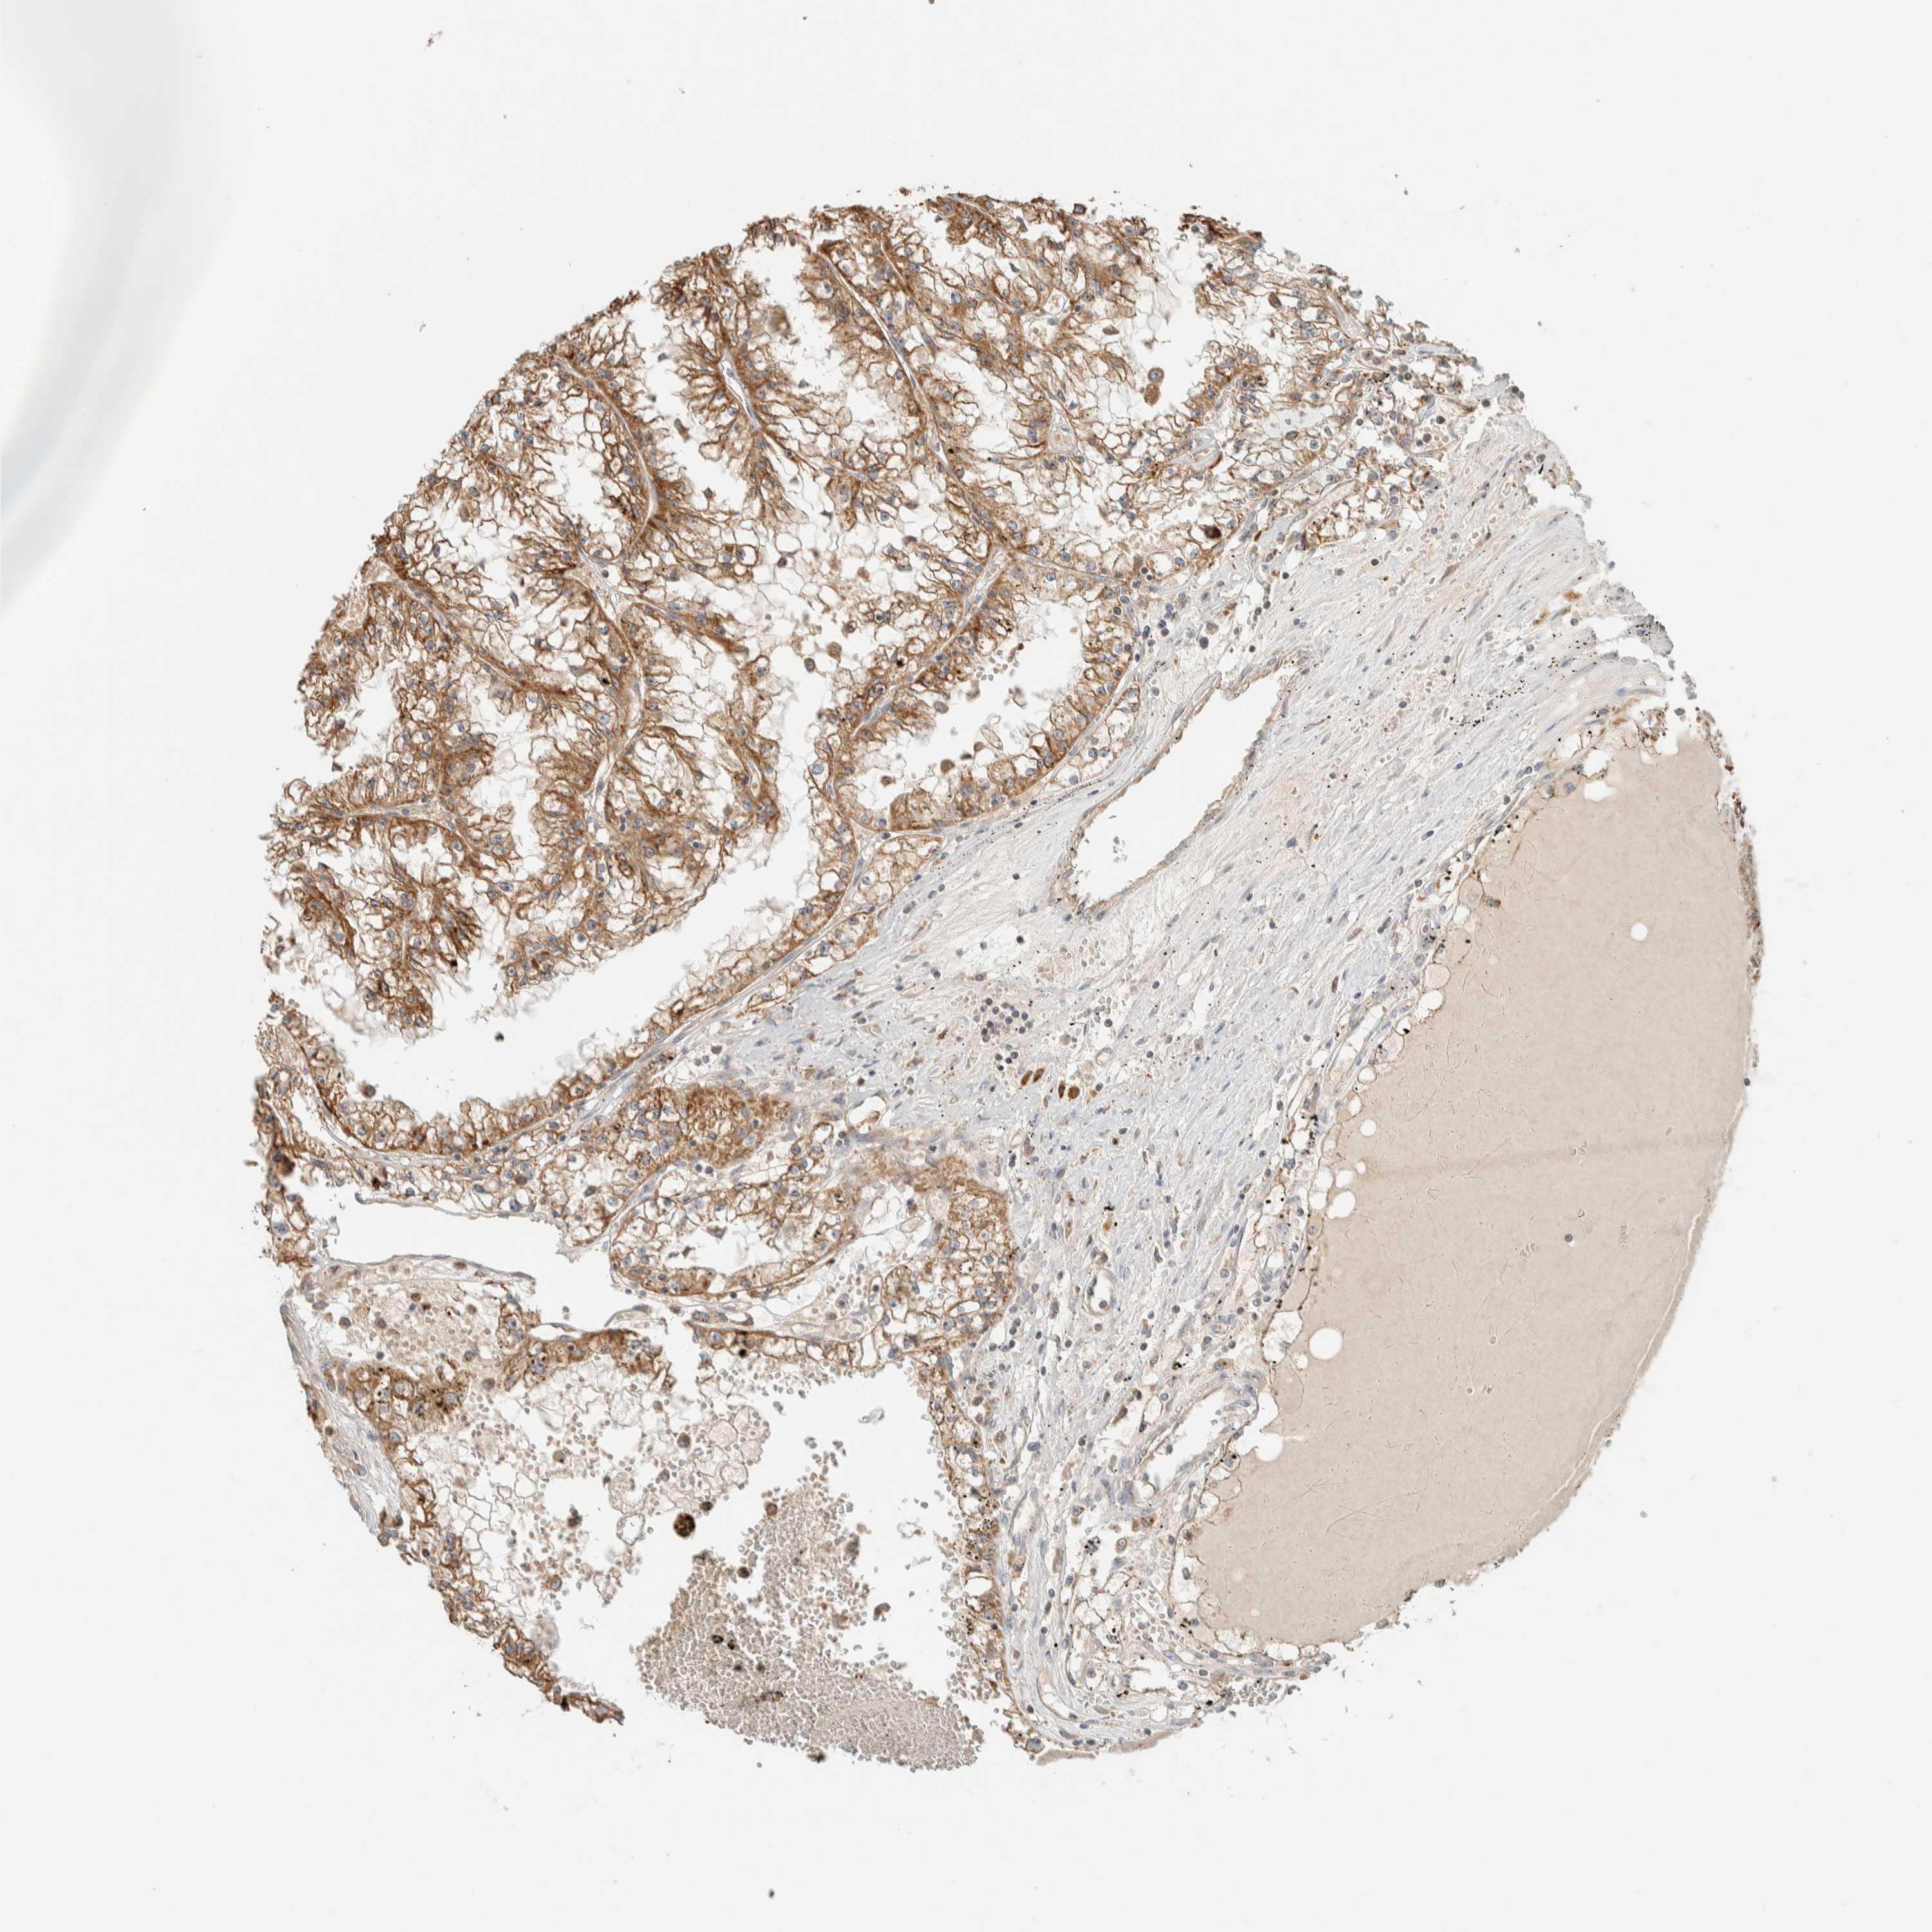

CANCER RENAL CANCER Show tissue menu

KICH TCGA KIRC TCGA KIRC VALIDATION KIRP TCGA PROTEIN RCC CPTAC PROTEIN EXPRESSION

Renal cancer